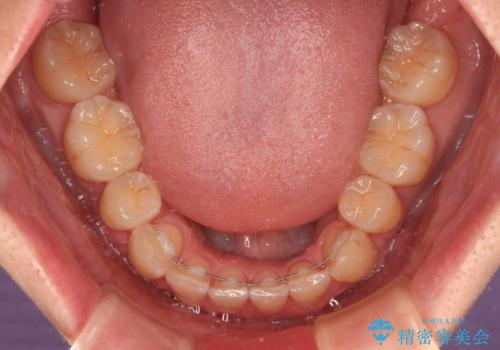

下顎骨が左側に大きく変位しているため、上下の正中位置は極力一致するところをゴールとしました。

上下顎で左右差の大きい抜歯矯正を裏側装置で行ったため、非常に時間がかかりましたが、正中位置も良い位置に改善され、気になっていた突出感も解消されました。